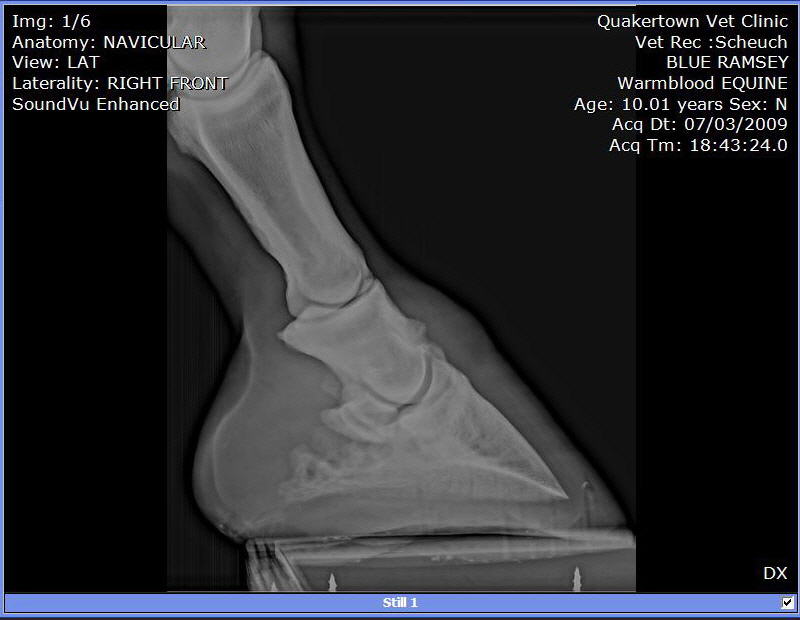

Posted on Sunday, Oct 28, 2012 - 6:53 pm: 10 year old performance horse, jumped into the ground. After, a few years barefoot, and on pasture rest, he is comfortable again. He doesn't have the survival instinct to buck a rider off when he is in pain. He just does his best to perform. He lives to perform. Why would anyone shoot a horse like this up? To make him feel better? Really? |

| Member: gramsey1 |

Posted on Sunday, Oct 28, 2012 - 7:22 pm: He how he looks today, but it was a long haul. Note the nasty brand redo; somebody wanted to hide is past. Rescued from a kill pen by a buyer that saw something special in him. You obviously get it. Isn't it nice to know your horse won't end up destroyed, looking for a lucky break? One can only imagine what he could have been, if owned early, by someone like "R" Trotter friend. |